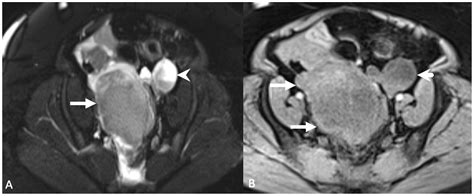

Magnetic Resonance Imaging (MRI)

MRI is a powerful imaging tool that provides high-resolution images of the pelvic structures. It can be used to evaluate the Ovarian Suspensory Ligament and detect abnormalities such as inflammation, tumors, or vascular compromise. MRI is particularly useful in cases of suspected ovarian torsion or cancer.